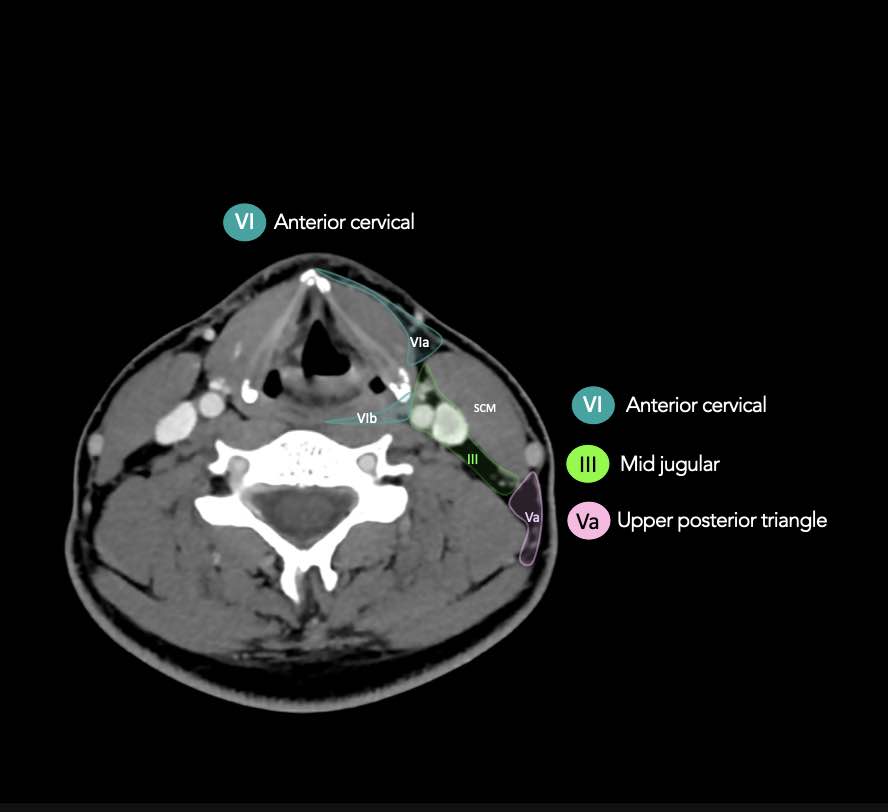

CT Scan Mặt Cắt Ngang (Axial CT)

Các lát cắt CT mặt phẳng ngang tương ứng với hình minh họa tổng quan.

Các lát cắt CT mặt phẳng ngang với hình ảnh chi tiết hơn.

Nhấp vào hình ảnh để phóng to.

III – Tĩnh mạch cảnh giữa

Tầng III nhận các bạch mạch hướng tâm từ tầng II và V, và một số bạch mạch hướng tâm từ các hạch sau hầu, trước khí quản và thần kinh thanh quản quặt ngược.

Tầng này thu nhận bạch huyết từ đáy lưỡi, amidan, thanh quản, hạ hầu và tuyến giáp.

Bờ dưới của sụn nhẫn là ranh giới giữa tầng III và tầng IVA.

Các hạch bạch huyết ở tầng III có nguy cơ chứa di căn từ các ung thư khoang miệng, vòm hầu, hầu miệng, hạ hầu và thanh quản.

VI – Cổ trước

Tầng này chứa các hạch tĩnh mạch cảnh trước nông (tầng VIa) và các hạch sâu hơn bao gồm hạch trước thanh quản, trước khí quản, cạnh khí quản và hạch thần kinh thanh quản quặt ngược (tầng VIb).